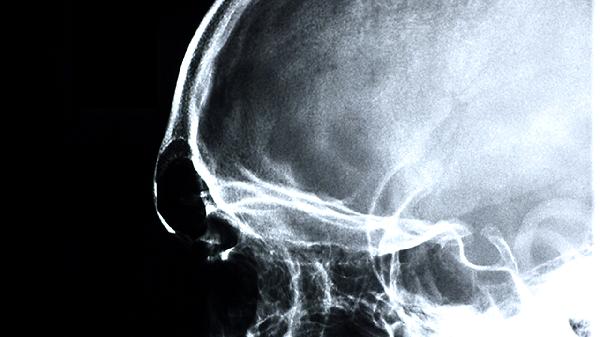

骨瘤可能与遗传或骨骼异常增生有关,通常表现为无痛性骨性突起等症状。良性骨瘤若无症状可观察随访,生长迅速或影响外观时需手术切除。术后需定期复查X线,排除恶变可能。